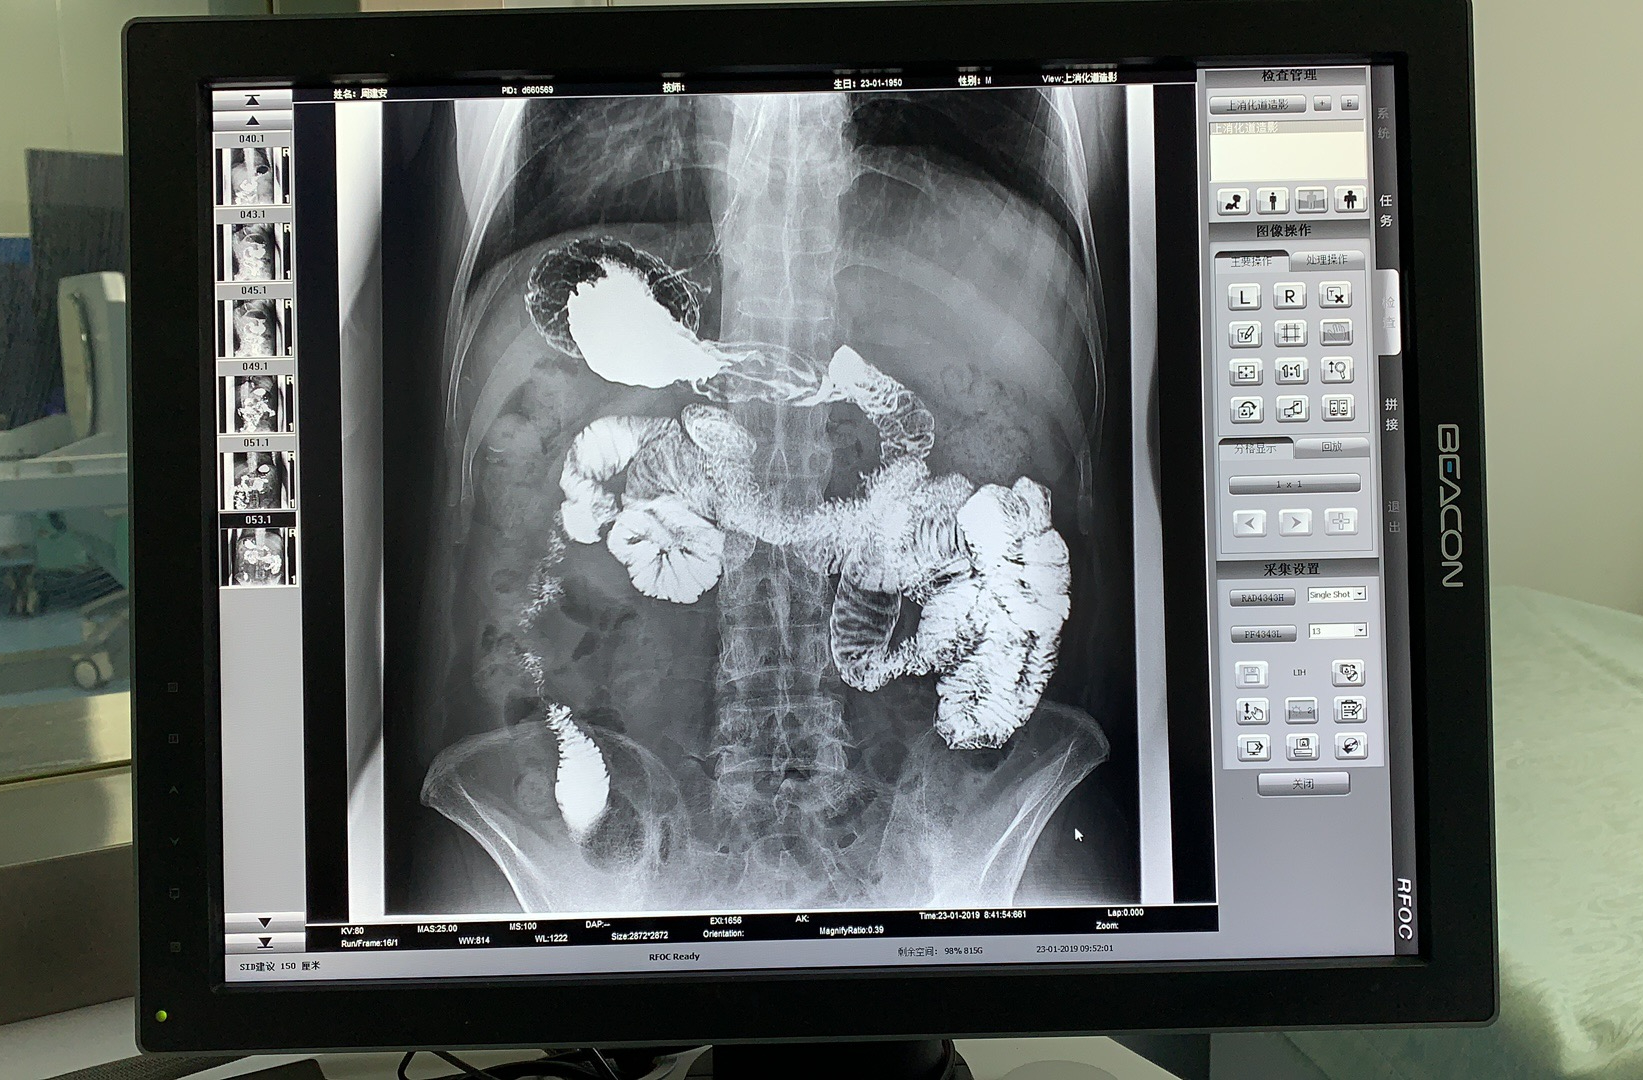

X 線檢查是肛腸疾病早期發(fā)現(xiàn)和診斷最有效的手段之一,隨著數(shù)字化技術(shù)的發(fā)展,可視化動(dòng)態(tài)DRF的出現(xiàn)為肛腸疾病患者帶來了更加精準(zhǔn)、舒適、方便的檢查方式。